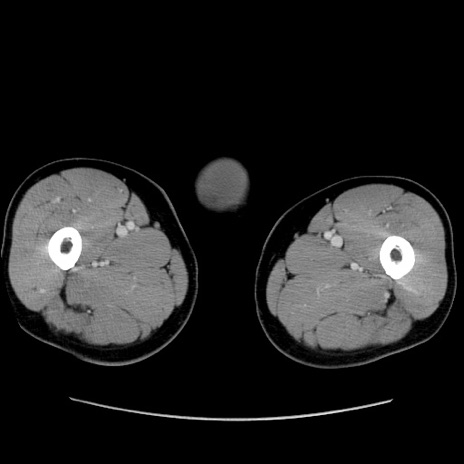

矢状断像

【症例】60歳代 男性

【主訴】右鼠径部膨隆

【現病歴】1年程前より右鼠径部膨隆あり。自己にて還納可能だったため放置していた。3時間前より右鼠径部の脱出を認め、還納困難となり受診。

【既往歴】高血圧

【身体所見】右鼠径部に小児頭大の膨隆あり。弾性硬であり、用手還納は困難。左鼠径部にも膨隆を認める。脱出はなし。

【データ】WBC 15500、CRP 測定なし